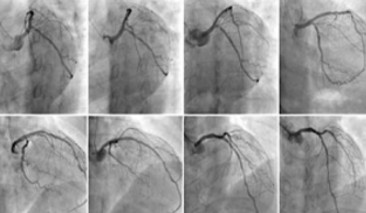

科室目前共有人員20余人,其中醫(yī)生10人,護(hù)理人員10余人,醫(yī)生正高職稱3人,中級(jí)職稱2人,初級(jí)職稱5人。科室定期邀請(qǐng)國內(nèi)知名專家授課,并派科內(nèi)中青年業(yè)務(wù)骨干輪流到國內(nèi)著名醫(yī)院進(jìn)修學(xué)習(xí),定期參加國內(nèi)重要的心血管學(xué)術(shù)會(huì)議??剖曳e極與國際全新診療技術(shù)接軌,在濰城區(qū)率先開展了冠狀動(dòng)脈造影、PCI、起搏器植入術(shù)等技術(shù),成功搶救了大量急性心肌梗死、病竇綜合征、三度房室傳導(dǎo)阻滯、心臟驟停等急危重癥患者。

冠心病介入診療中心

心血管內(nèi)科在心血管首席專家、學(xué)科帶頭人韓海英主任醫(yī)師的帶領(lǐng)下,秉著“生命所系、健康所托”的宗旨,傳承著“時(shí)間就是心肌,心肌就是生命”的白衣天使的誓言,一直致力于挽救患者生命及提高患者生活質(zhì)量,建立急性胸痛處理的綠色通道,成功挽救了成千上萬患者的生命,為挽救壞死心肌做出了最大的努力。醫(yī)院特聘原濰坊市人民醫(yī)院急診科張言鎮(zhèn)主任為心內(nèi)科首席專家,大力開展冠狀動(dòng)脈介入治療,為挽救更多心肌梗死病人提供最快、最優(yōu)、最佳的治療方案。